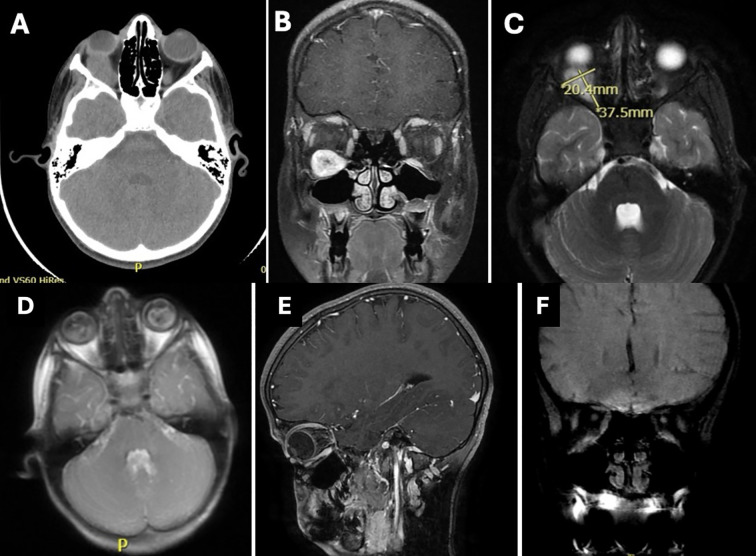

Orbital schwannomas are benign tumors that arise from Schwann cells in the peripheral nerves in the orbit. They typically present after the second decade of life given their slow growth and rarely before then. Diagnosis is based on clinical course and specific imaging modalities; however, the definitive diagnosis is by lesion biopsy. Surgical removal is typically curative. Herein we present the case of an 8-year-old boy with proptosis and diplopia where he exhibited the clinical findings of an orbital mass, however, the characteristic picture of orbital schwannoma was observed on imaging yet found within the inferior rectus muscle, a rare finding indeed.